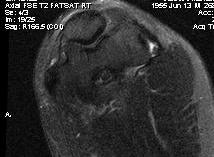

MRI

High grade partial tears of ECRB on lateral eipcondyle

Tendonopathy of the common extensor origin, with thickening and high grade tear partial tear